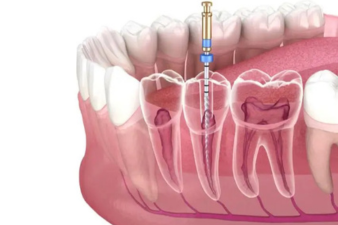

علاج العصب